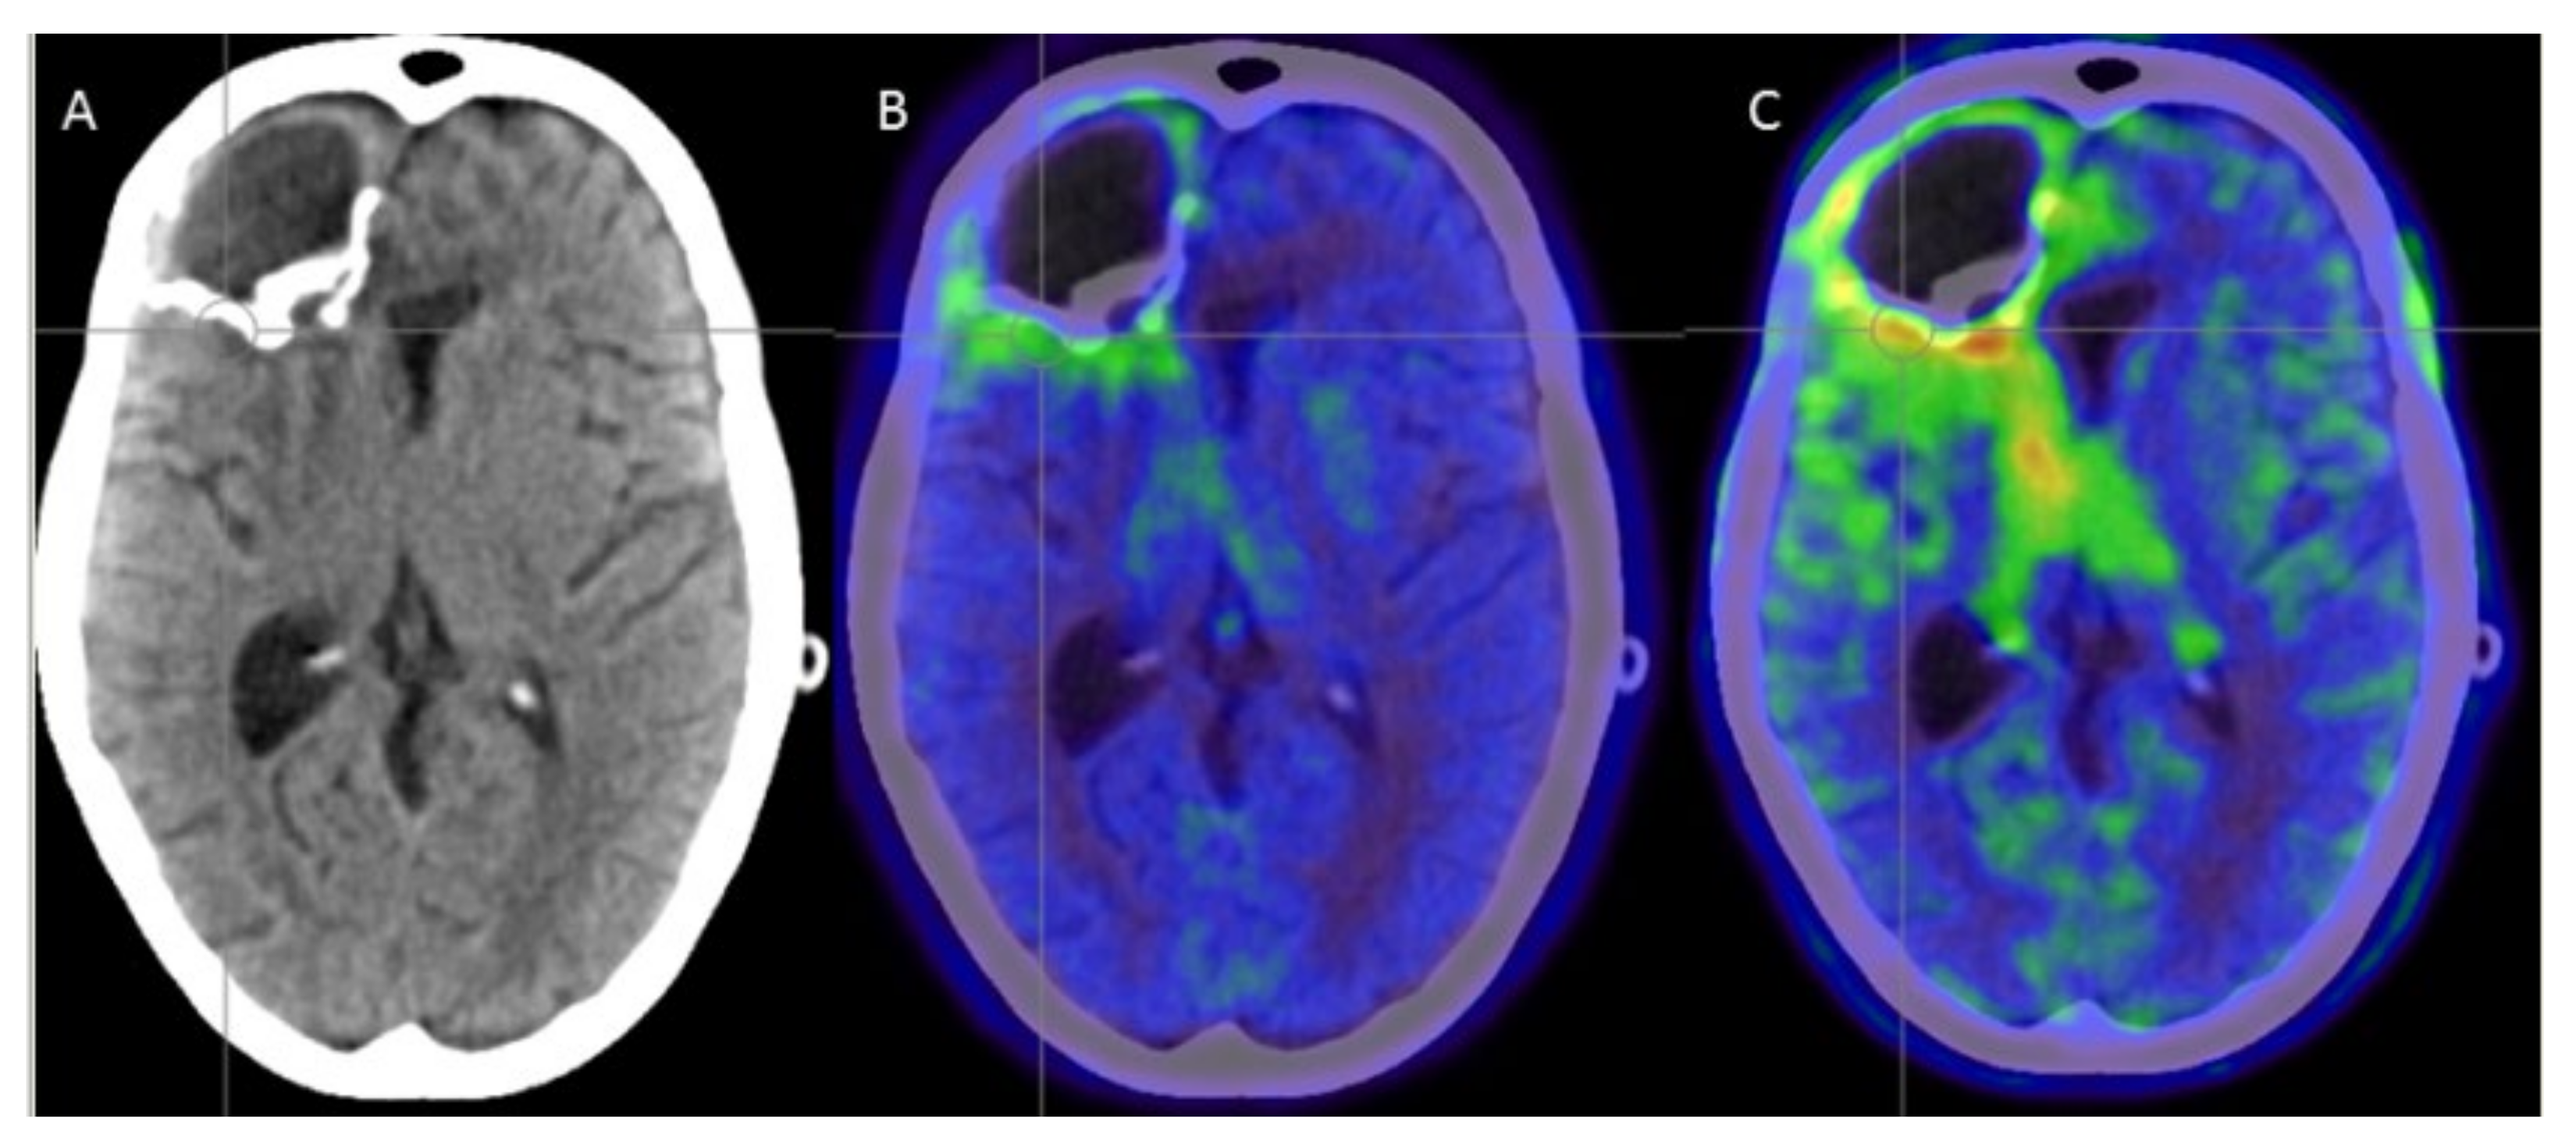

- Plotkin, M.; Gneveckow, U.; Meier-Hauff, K.; Amthauer, H.; Feußner, A.; Denecke, T.; Gutberlet, M.; Jordan, A.; Felix, R.; Wust, P. 18F-FET PET for planning of thermotherapy using magnetic nanoparticles in recurrent glioblastoma. Int. J. Hyperth. 2006, 22, 319–325. [Google Scholar] [CrossRef]